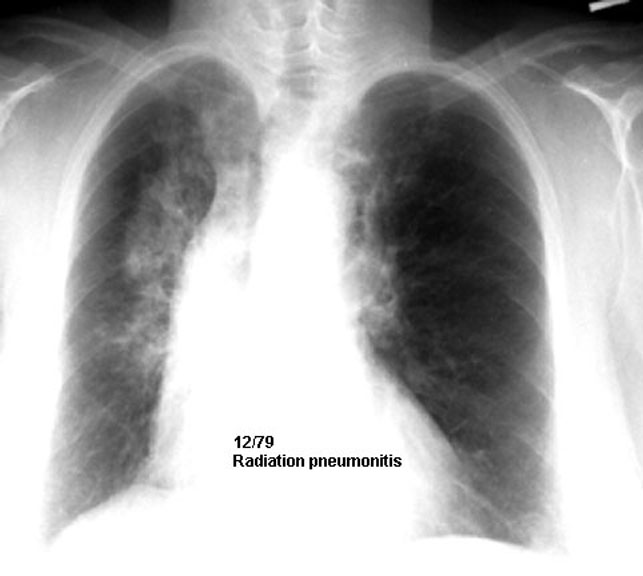

Radiation pneumonitis corresponding to radiation port.

Note vertical line of demarcation corresponding to radiation port.